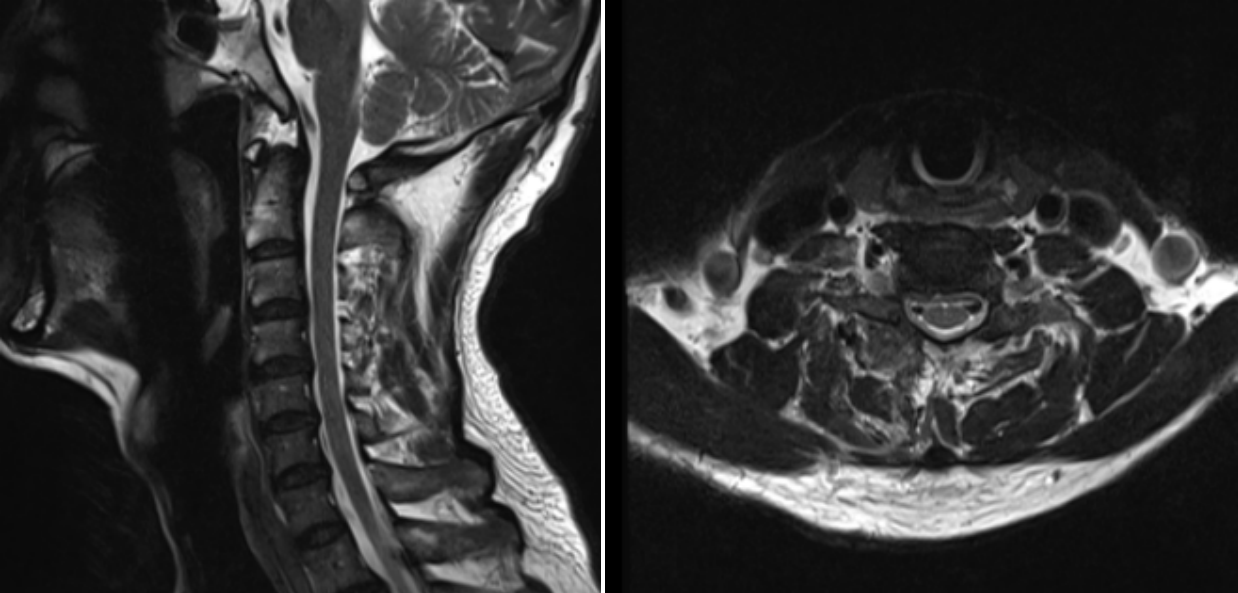

術(shù)后第一天MRI圖像

術(shù)后效果立竿見影,患者的疼痛癥狀得到了顯著緩解,麻木感也逐漸消退。術(shù)后1天,患者便能在醫(yī)護人員的指導(dǎo)下下床活動。經(jīng)過3天的觀察與護理,患者身體狀況良好,順利出院,手術(shù)取得圓滿成功。